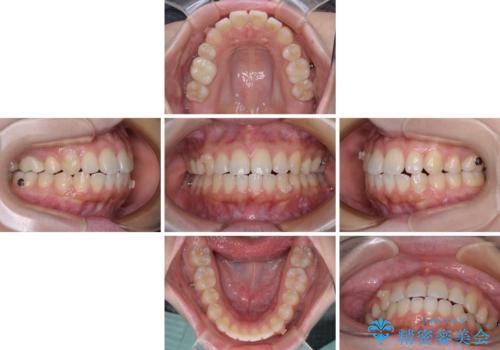

再矯正 開咬に後戻りした歯列をインビザラインで改善

デコボコと上下前歯の隙間が気になるものの、しっかりと治療をしたいという意思はないとのことで、インビザラインの中でもアライナー数に制約のあるライトパッケージを用いて、治療できる範囲まで歯列を改善していくこととしました。

インビザラインは前歯部の開咬に効果的であることが多く、ライトパッケージにもかかわらず、十分満足のいく仕上がりとなりました。